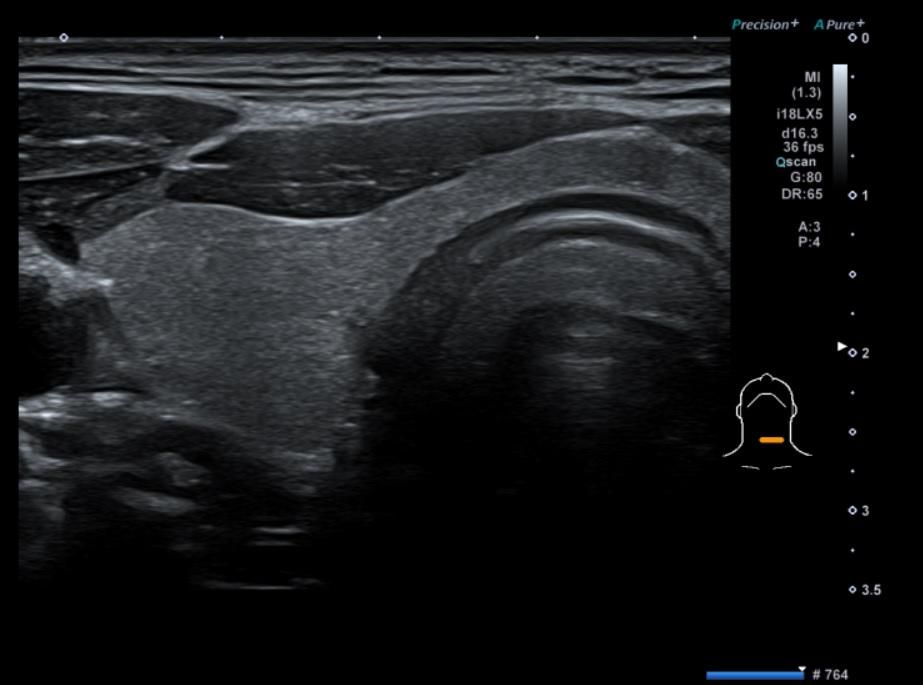

• 3번 째 사진